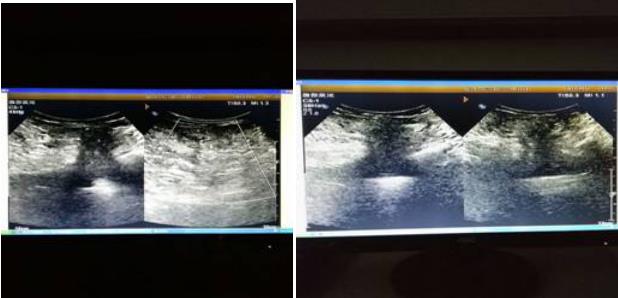

超聲所見(jiàn):右下腹患者自述“腫物”處探查:距體表約0.8㎝處,探及長(zhǎng)度約14.8㎝不均質(zhì)偏強(qiáng)回聲,中心部較大厚度5.4㎝,邊界清晰,于該腫物后方探及寬度約2.8㎝似為回聲失落處,于該處偏內(nèi)側(cè)探及股動(dòng)靜脈。右側(cè)腹股溝區(qū)探及扁橢圓形淋巴結(jié),較大者0.77*0.56/0.8*0.5㎝。

診斷意見(jiàn):右下腹部近腹股溝區(qū)偏強(qiáng)回聲腫物--考慮為股疝,內(nèi)為網(wǎng)膜可能,因腫物巨大探查受限,不除外其他,請(qǐng)結(jié)合其他檢查。

后經(jīng)臨床手術(shù)證實(shí),為右側(cè)巨大股疝,內(nèi)容物為大網(wǎng)膜。

超聲表現(xiàn):疝囊位置是超聲診斷股疝的重要依據(jù)。根據(jù)股疝疝囊大小及內(nèi)容物的不同,其超聲表現(xiàn)略有差別。典型股疝的疝囊一般較小,常位于腹股溝韌帶下方的股內(nèi)側(cè),其外側(cè)為股靜脈;若疝囊較大時(shí),可移位至腹股溝韌帶上方或恥骨聯(lián)合處。仔細(xì)檢查可見(jiàn)疝囊于腹股溝韌帶后方經(jīng)較窄的頸部與腹腔相通;咳嗽或乏氏運(yùn)動(dòng)時(shí),疝囊大小可略有增大或無(wú)顯著變化。疝囊內(nèi)容物可為網(wǎng)膜組織,呈中強(qiáng)回聲;也可為腸管,聲像圖顯示為管腔樣結(jié)構(gòu);若病程較長(zhǎng)時(shí),疝囊內(nèi)可見(jiàn)無(wú)回聲積液。股疝嵌頓時(shí),疝囊內(nèi)腸管腫脹壓痛,可同時(shí)伴有腹腔內(nèi)腸管擴(kuò)張。鑒別診斷